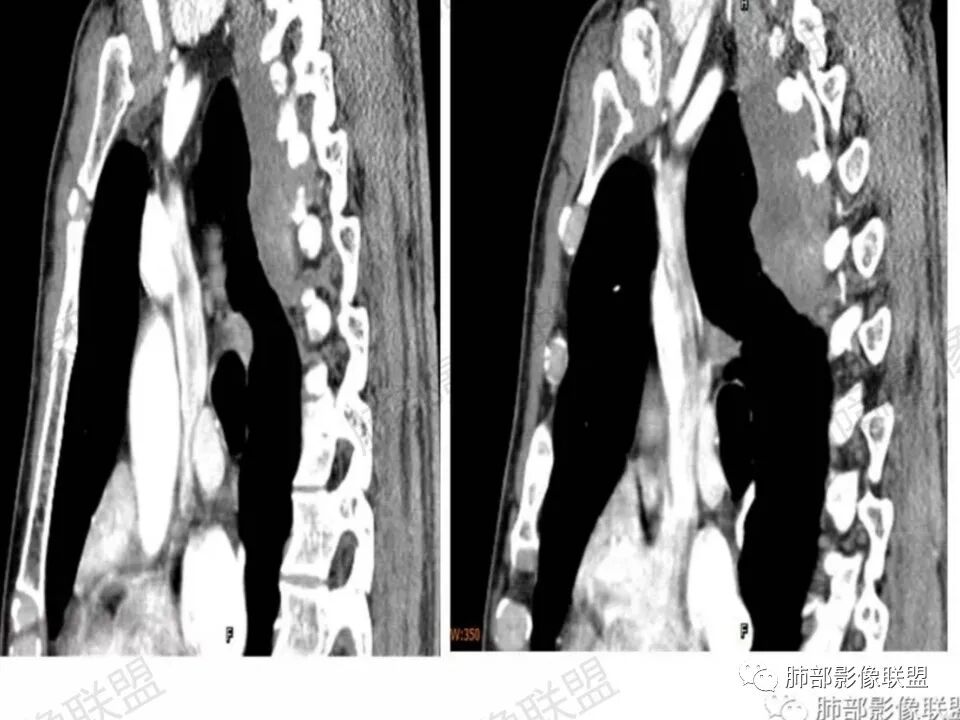

问:这个病例病灶确实邻近椎间孔生长,除了神经源性肿瘤会向椎间孔方向生长,还有什么肿瘤会有这种行为?这个病灶整体形态呈扁平不规则,周围骨质未见破坏,就一定是良性吗?    答:这个病灶明显嵌入式生长,往往提示病灶柔软或有侵袭性,而神经鞘瘤往往有包膜,有张力,典型的形态往往呈类圆形、“逗点形”或“哑铃型”横向延入某一椎间孔内;神经节细胞瘤虽然可以比较柔软,但是具有大量粘液基质,动静脉期强化不明显,延迟强化轻度增强,加之没有钙化,故符合点不多;此外比较柔软的肿瘤如淋巴瘤,但是周围没有肿大淋巴结不太考虑;本例形态不规则的实性肿块,没有明显骨质破坏,倾向具有侵袭性的间叶来源的肿瘤。

答:神经源性肿瘤的解剖位置及形态很重要—沿神经干方向生长走行。后纵膈内神经鞘瘤最常见的是神经根出入椎间孔处,并可沿着肋间神经方向分布,所以后纵膈神经鞘瘤通常横径大,上下径小,这个病例明显上下径长,所以不符合神经鞘瘤;神经节细胞瘤可沿着椎旁上下方向分布(参见上图黄色梭形的神经节),所以表现为上下径长,虽然生长方式符合,但是节细胞瘤以粘液为主,易钙化,该病例成分及强化方式不符合。